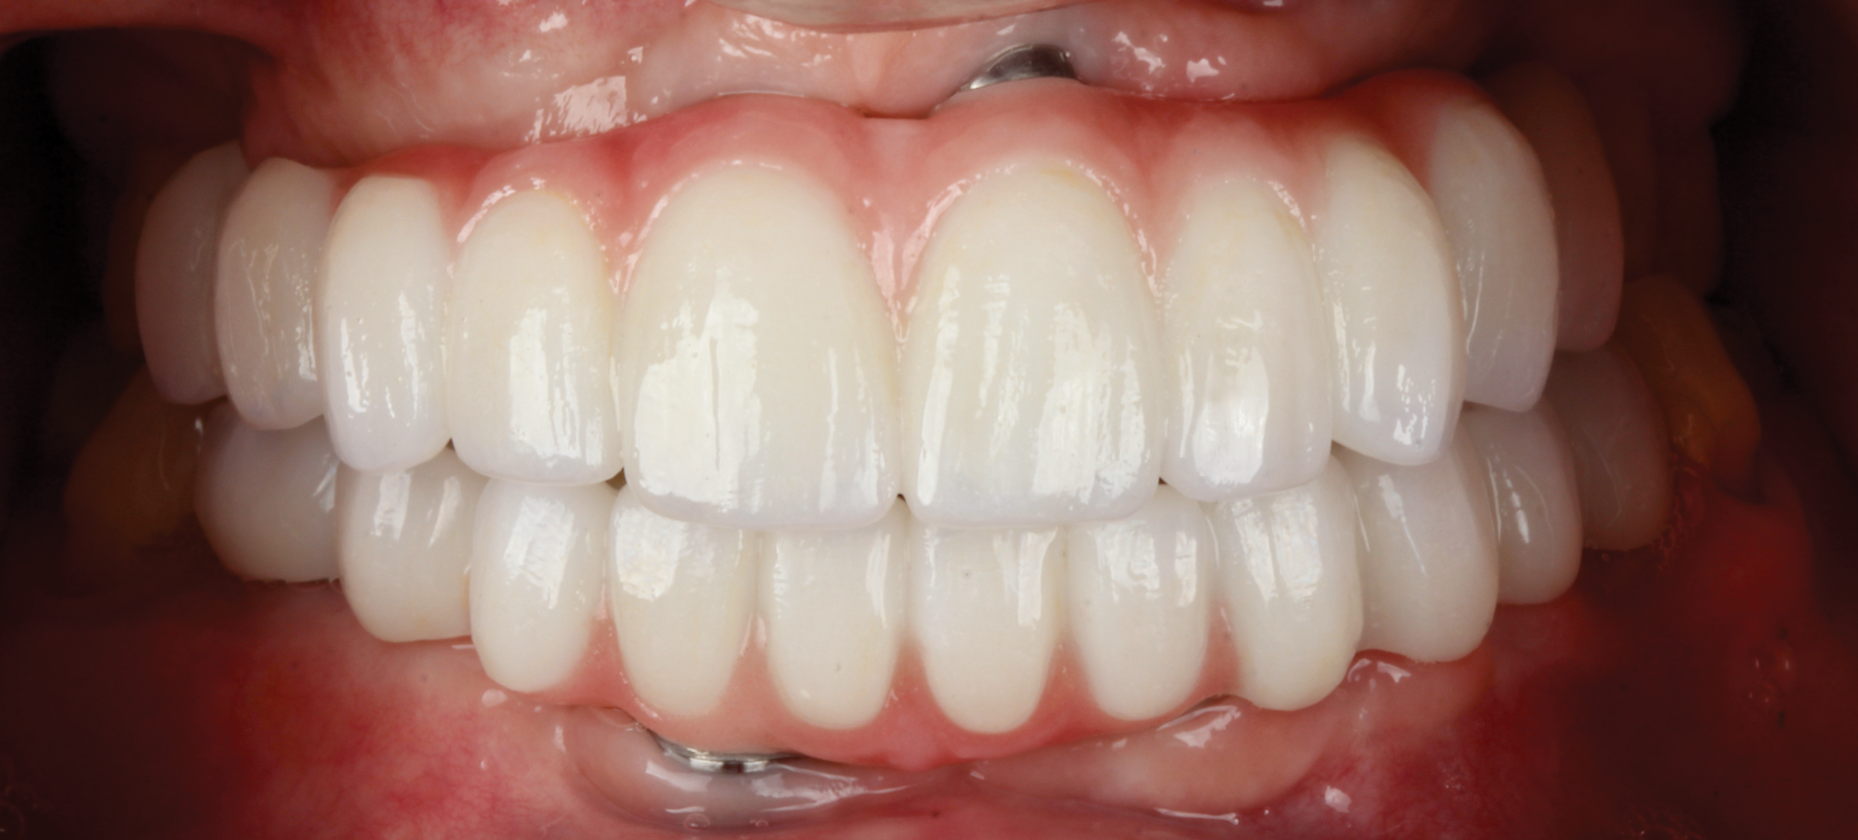

Five individual screw-retained milled ceramic crowns completed the all-digital treatment used to restore the patient without complication. As indicated in photographs taken at delivery of the final prostheses, the wholly digitally planned and executed restoration achieved a completely technological, natural-appearing outcome, and the patient was extremely satisfied (Figure 6).

Fig 6. Final outcome at delivery of screw-retained milled ceramic crown restorations.

Figure 6